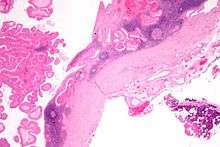

Histopathology of Warthin tumor in the parotid gland. H&E stain.

Histopathology of Warthin tumor in the parotid gland. Another view of a file "Warthin tumor (1).jpg". H&E stain.

Histopathology of Warthin tumor in the parotid gland. Higher magnification of a file "Warthin tumor (1).jpg". H&E stain.

Intermediate magnification micrograph of a Warthin tumor.

High magnification micrograph of a Warthin tumor showing the characteristic bilayered epithelium.

The appearance of this tumor under the microscope is unique. There are cystic spaces surrounded by two uniform rows of epithelial cells with centrally placed pyknotic nuclei. The cystic spaces have epithelium referred to as papillary infoldings that protrude into them. Additionally, the epithelium has lymphoid stroma with germinal center formation.